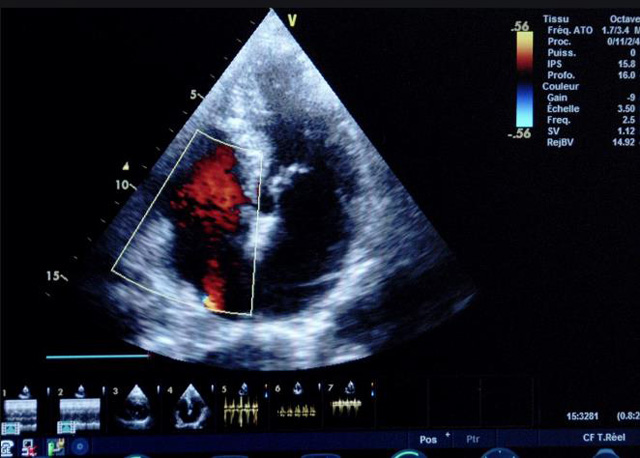

二、彩色室壁運動分析

(一)基本原理彩色室璧運動分析,從整體散射數據中識別心內膜邊界,并與前一幀彩色不同,心臟收縮或舒張期開始到結束時心內膜的全部過程。每一次順序顯示結束后,原來的彩色自動消失,以便進入下一個顯示過程。其結果是獲得對應于每一個心動周期的彩色顯示,描繪特定周期內室壁運動的時間運動軌跡。

(二)操作步驟根據背向散射數據中將心內膜運動的位移過程分類為組織或血液的原理,邊緣檢測跟蹤心內膜和血液的界面。橙色表示收縮期的開始,收縮期不同時相逐幀顯示色彩均疊加在收縮末期最后一幀圖像中。檢查時,可按以下步驟進行:

①顯示較為理想的二維圖像,常用切面有心尖四腔心、二腔心、左心室長軸和左心室乳頭肌水平短軸切面。

③啟動CK系統,啟動后劃定感興趣區域。同時記錄的心動圖R波頂點為舒張末期,T波終點為收縮末期,顯示RT間期的CK彩階圖,連續記錄3~ 5個心動周期。

(三)檢測節段性室壁運動異常,研究冠心病患者左心室功能和分析局部室壁運動過程中。測量每一節段室壁的運動量,運動正常的節段彩帶色彩均勻層次光整。運動減弱的節段,厚度薄層次不全。心內膜位移幅度和速度均減低。心內膜位移幅度和速度甚低或難以測得。正常的多層彩帶消失,呈現紅色色帶,心內膜位移呈負向,幅度和速度亦減低。急性心肌梗死的患者中可用于識別存活心肌抑或壞死心肌。多巴酚丁胺負荷試驗存活心肌的心內膜位移幅度增高,停藥后即消失,而壞死心肌則無上述表現。實時檢查冠心病的節段性室壁運動異常,有時候通過發現局部心肌運動的時相異常,對于心臟傳導障礙的診斷也可能有幫助。